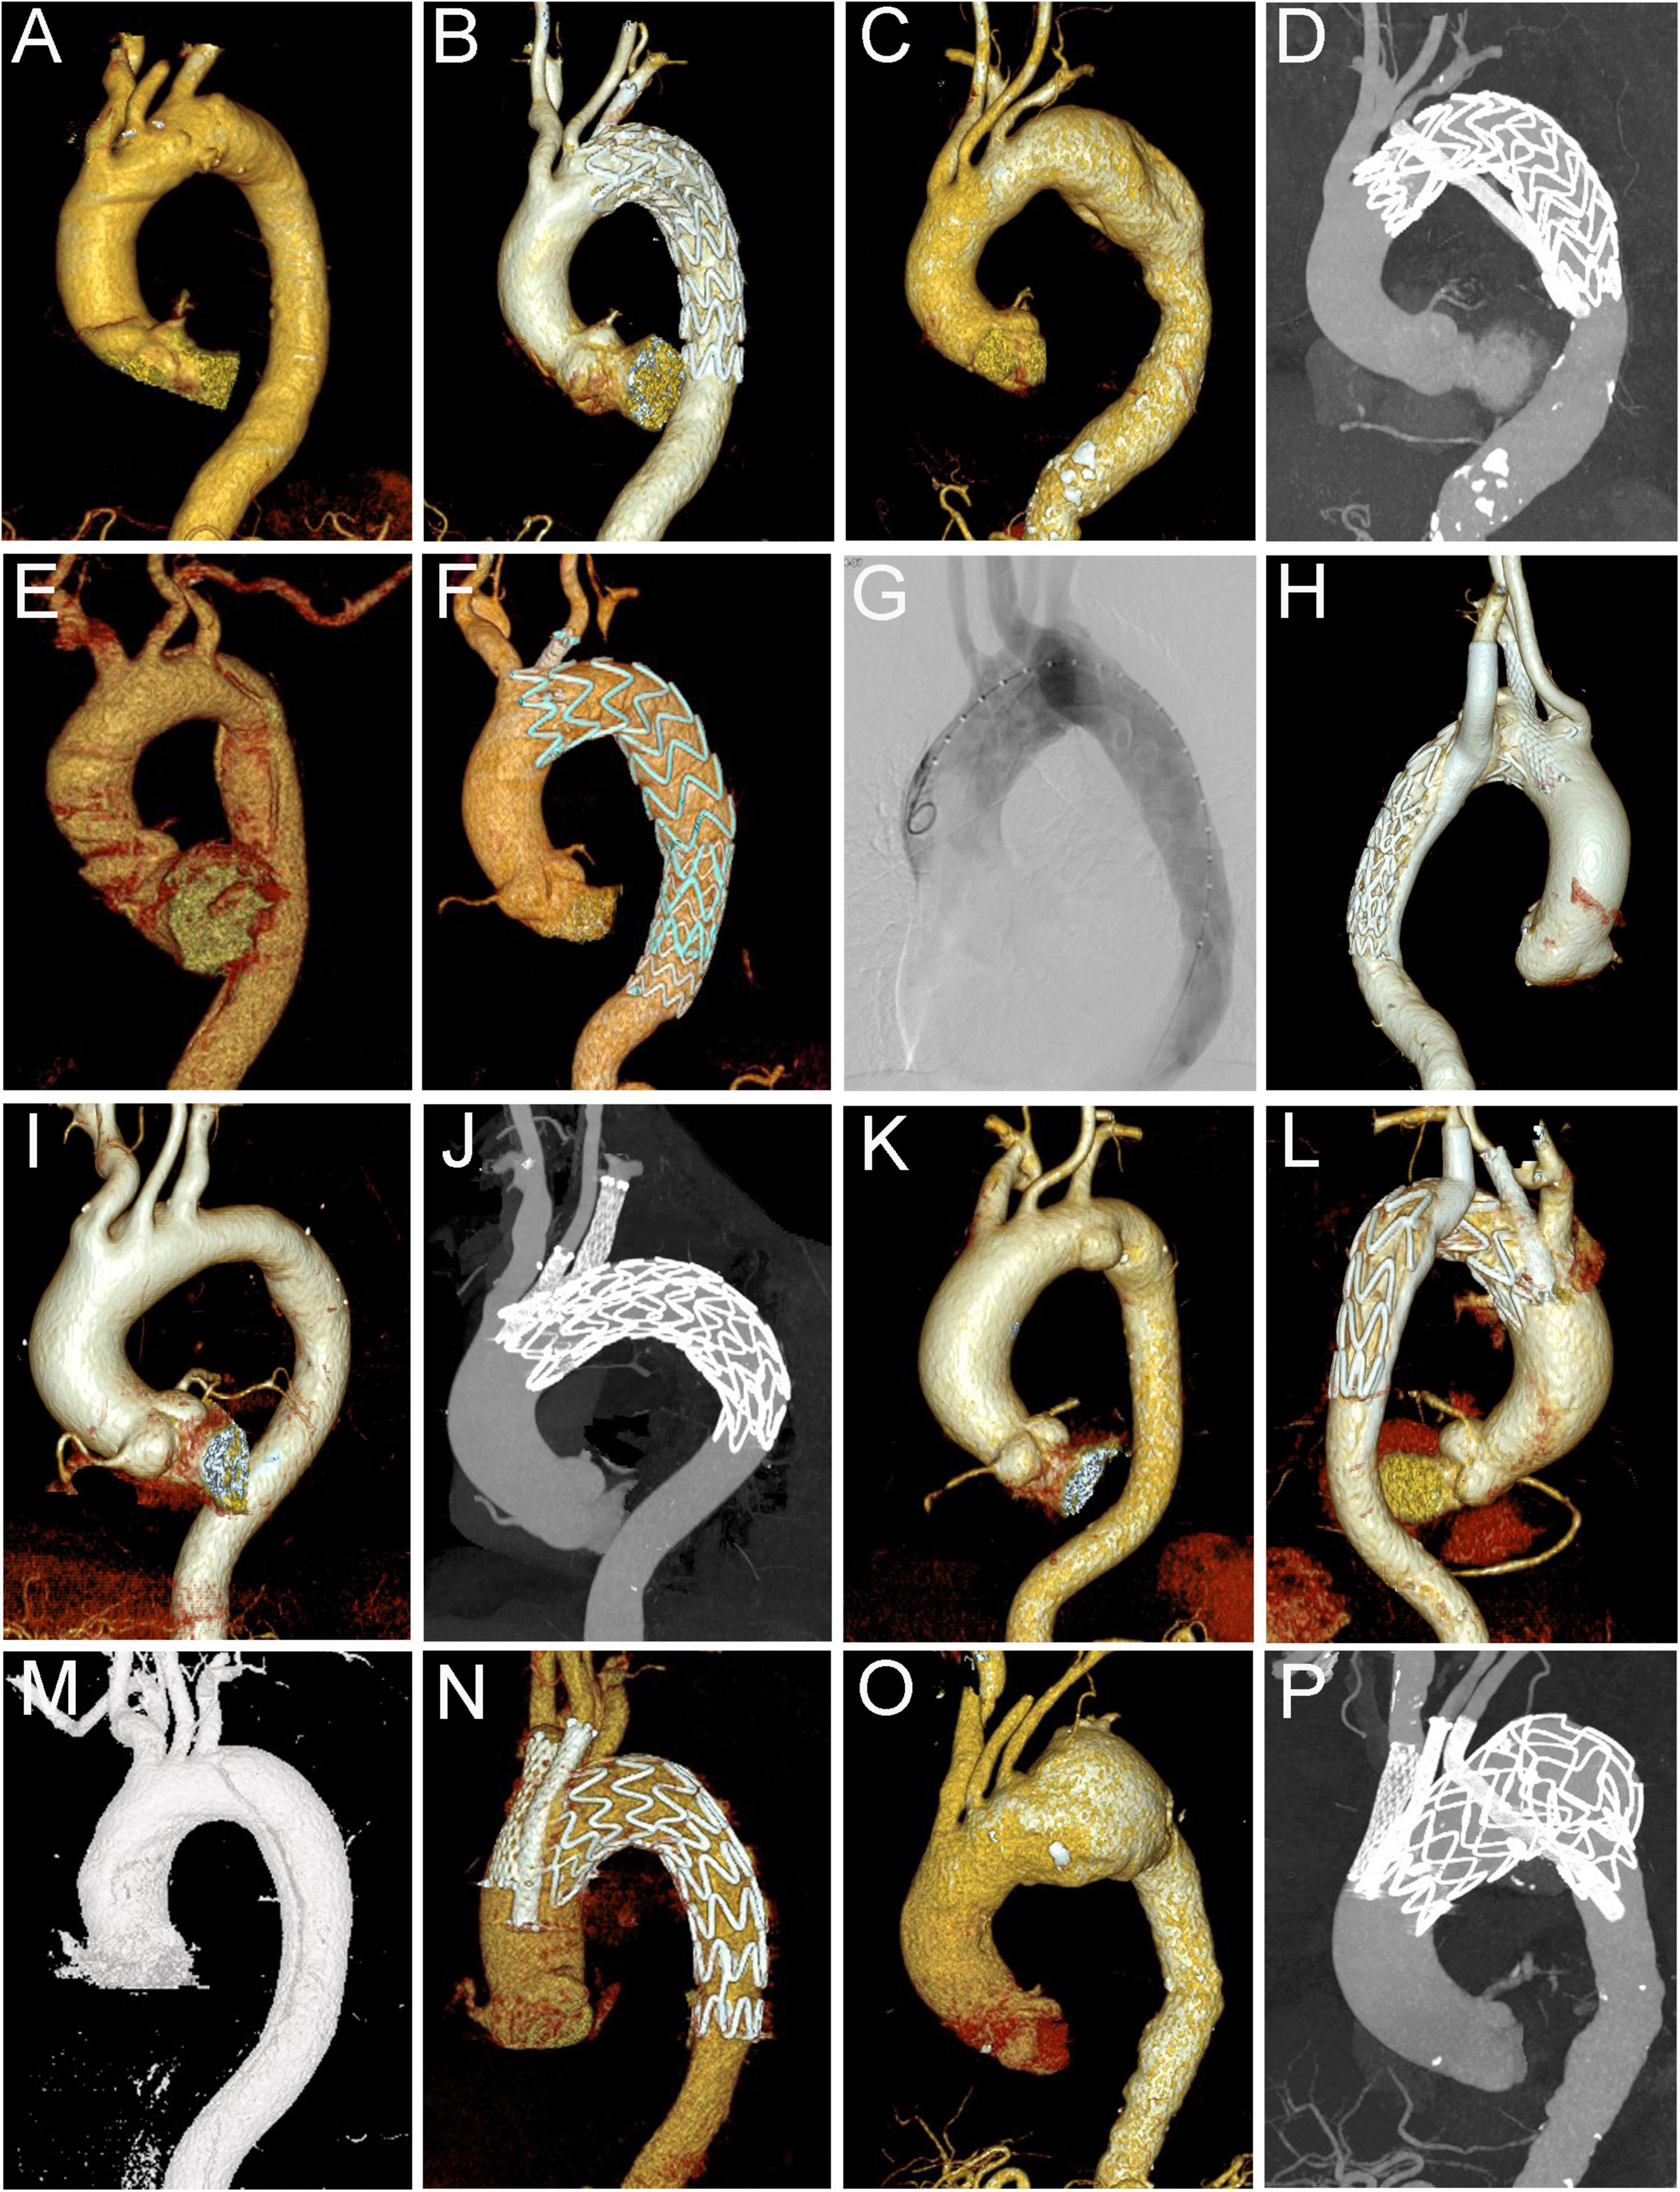

Methods: From November 2007 to June 2021, a total of 345 consecutive patients (mean age 56 ± 11.3 years, range 28–83, 302 men) with aortic arch pathologies underwent TEVAR combined with chimney technique (cTEVAR). Their medical data and follow-up results were retrospectively reviewed and analyzed.

Results: Among the 345 patients, 278 (80.6%) received single chimneys, 53 (15.4%) received double chimneys, 7 (2%) received triple chimneys, and 7 (2%) underwent cTEVAR accompanied by other techniques (two with extra-anatomical bypass, two with in situ fenestration, and three with physician modified fenestration). A total of 412 chimney stents were used, including 27 in the innominate artery (IA), 113 in the left common carotid artery, 270 in the left subclavian artery, and two in the aberrant right subclavian artery. Early type IA endoleaks were found in 38 (11%) patients, including 12 with the double or triple chimney technique. Early type II endoleak was found in nine (2.6%) patients. Early re-intervention occurred in two patients with double chimney technique, one for chimney stent migration and the other for compression of chimney stent. The 30-day mortality was 1.2% (4 in 345). During a mean follow-up of 42 ± 22 months (range 1–108 months), major stroke occurred in nine (2.6%) patients, chimney occlusion or stenosis occurred in six (1.7%), and retrograde type A aortic dissection occurred in four (1.2%). Fourteen (4.1%) patients received the secondary intervention. The all-cause mortality was 6.7% (23 in 345). Additionally, the total adverse event rate after cTEVAR was 13.9% (48 in 345).